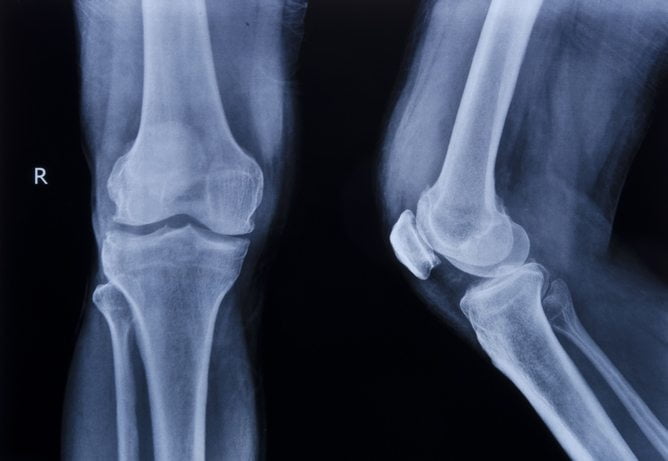

Лечить колено начинают только после того, как пациент прошел полное обследование. Выявление прямой и косвенных причин, вызывающих боли при сгибании ноги, станет основой правильного диагноза.

Обследование проходит с помощью следующих методов:

- Рентгенологические виды обследования.